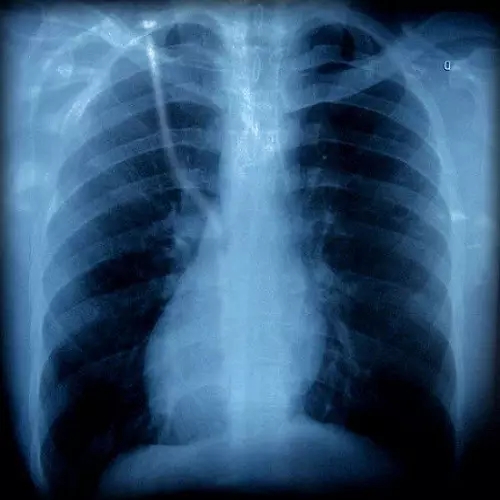

胸片有異

胸外科

咳嗽可以是由肺部腫瘤等疾病引起的,如果胸片或胸部CT上發(fā)現有可疑病變時(shí),應該看看胸外科。一般,呼吸內科大夫也會(huì )幫忙轉診的。